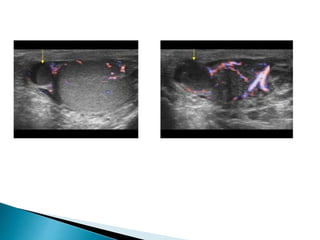

 On ultrasound varicoceles are seen as a

echo-free serpiginous structures measuring

more than 2 mm maximum diameter .

 Visible flow may he seen within larger

varicoceles.

 Their prominence is increased in the

upright position and with the Valsalva

manoeuvre.

 On ultrasoundvaricoceles are seen as a echo-free serpiginous structures measuring more than 2 mm maximum diameter .  Visible flow may he seen within larger varicoceles.  Their prominence is increased in the upright position and with the Valsalva manoeuvre.